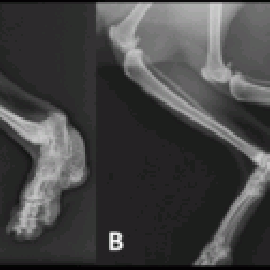

Bone abnormalities in Scottish Fold cats: ‘A’ shows a severely affected cat and ‘B’ a mildly affected cat (photo courtesy of Richard Malik)

- Osteochondrodysplasia (OD): This condition is linked to the genetic mutation responsible for the folded ears. It affects the development of cartilage and can lead to abnormal bone and joint growth. Cats with severe OD can experience pain, lameness, and difficulty moving if you Breed two folded-ear cats together, which can result in offspring with more severe forms of this condition.

Osteochondrodysplasia, commonly known as "Folded Ear Syndrome," is a genetic condition that affects the skeletal development of Scottish Fold cats. This condition is responsible for the distinctive folded ears that give the breed its unique appearance. However, it's important to note that while folded ears are a defining feature of the breed, the genetic mutation responsible for them can also be associated with certain health concerns. Here's a full description of osteochondrodysplasia in Scottish Fold cats:

Description: Osteochondrodysplasia is a hereditary genetic condition that primarily affects the cartilage and bone development of Scottish Fold cats. The most noticeable manifestation of this condition is the folding of the ears, where the ear cartilage does not fully develop, leading to the unique appearance that the breed is known for.